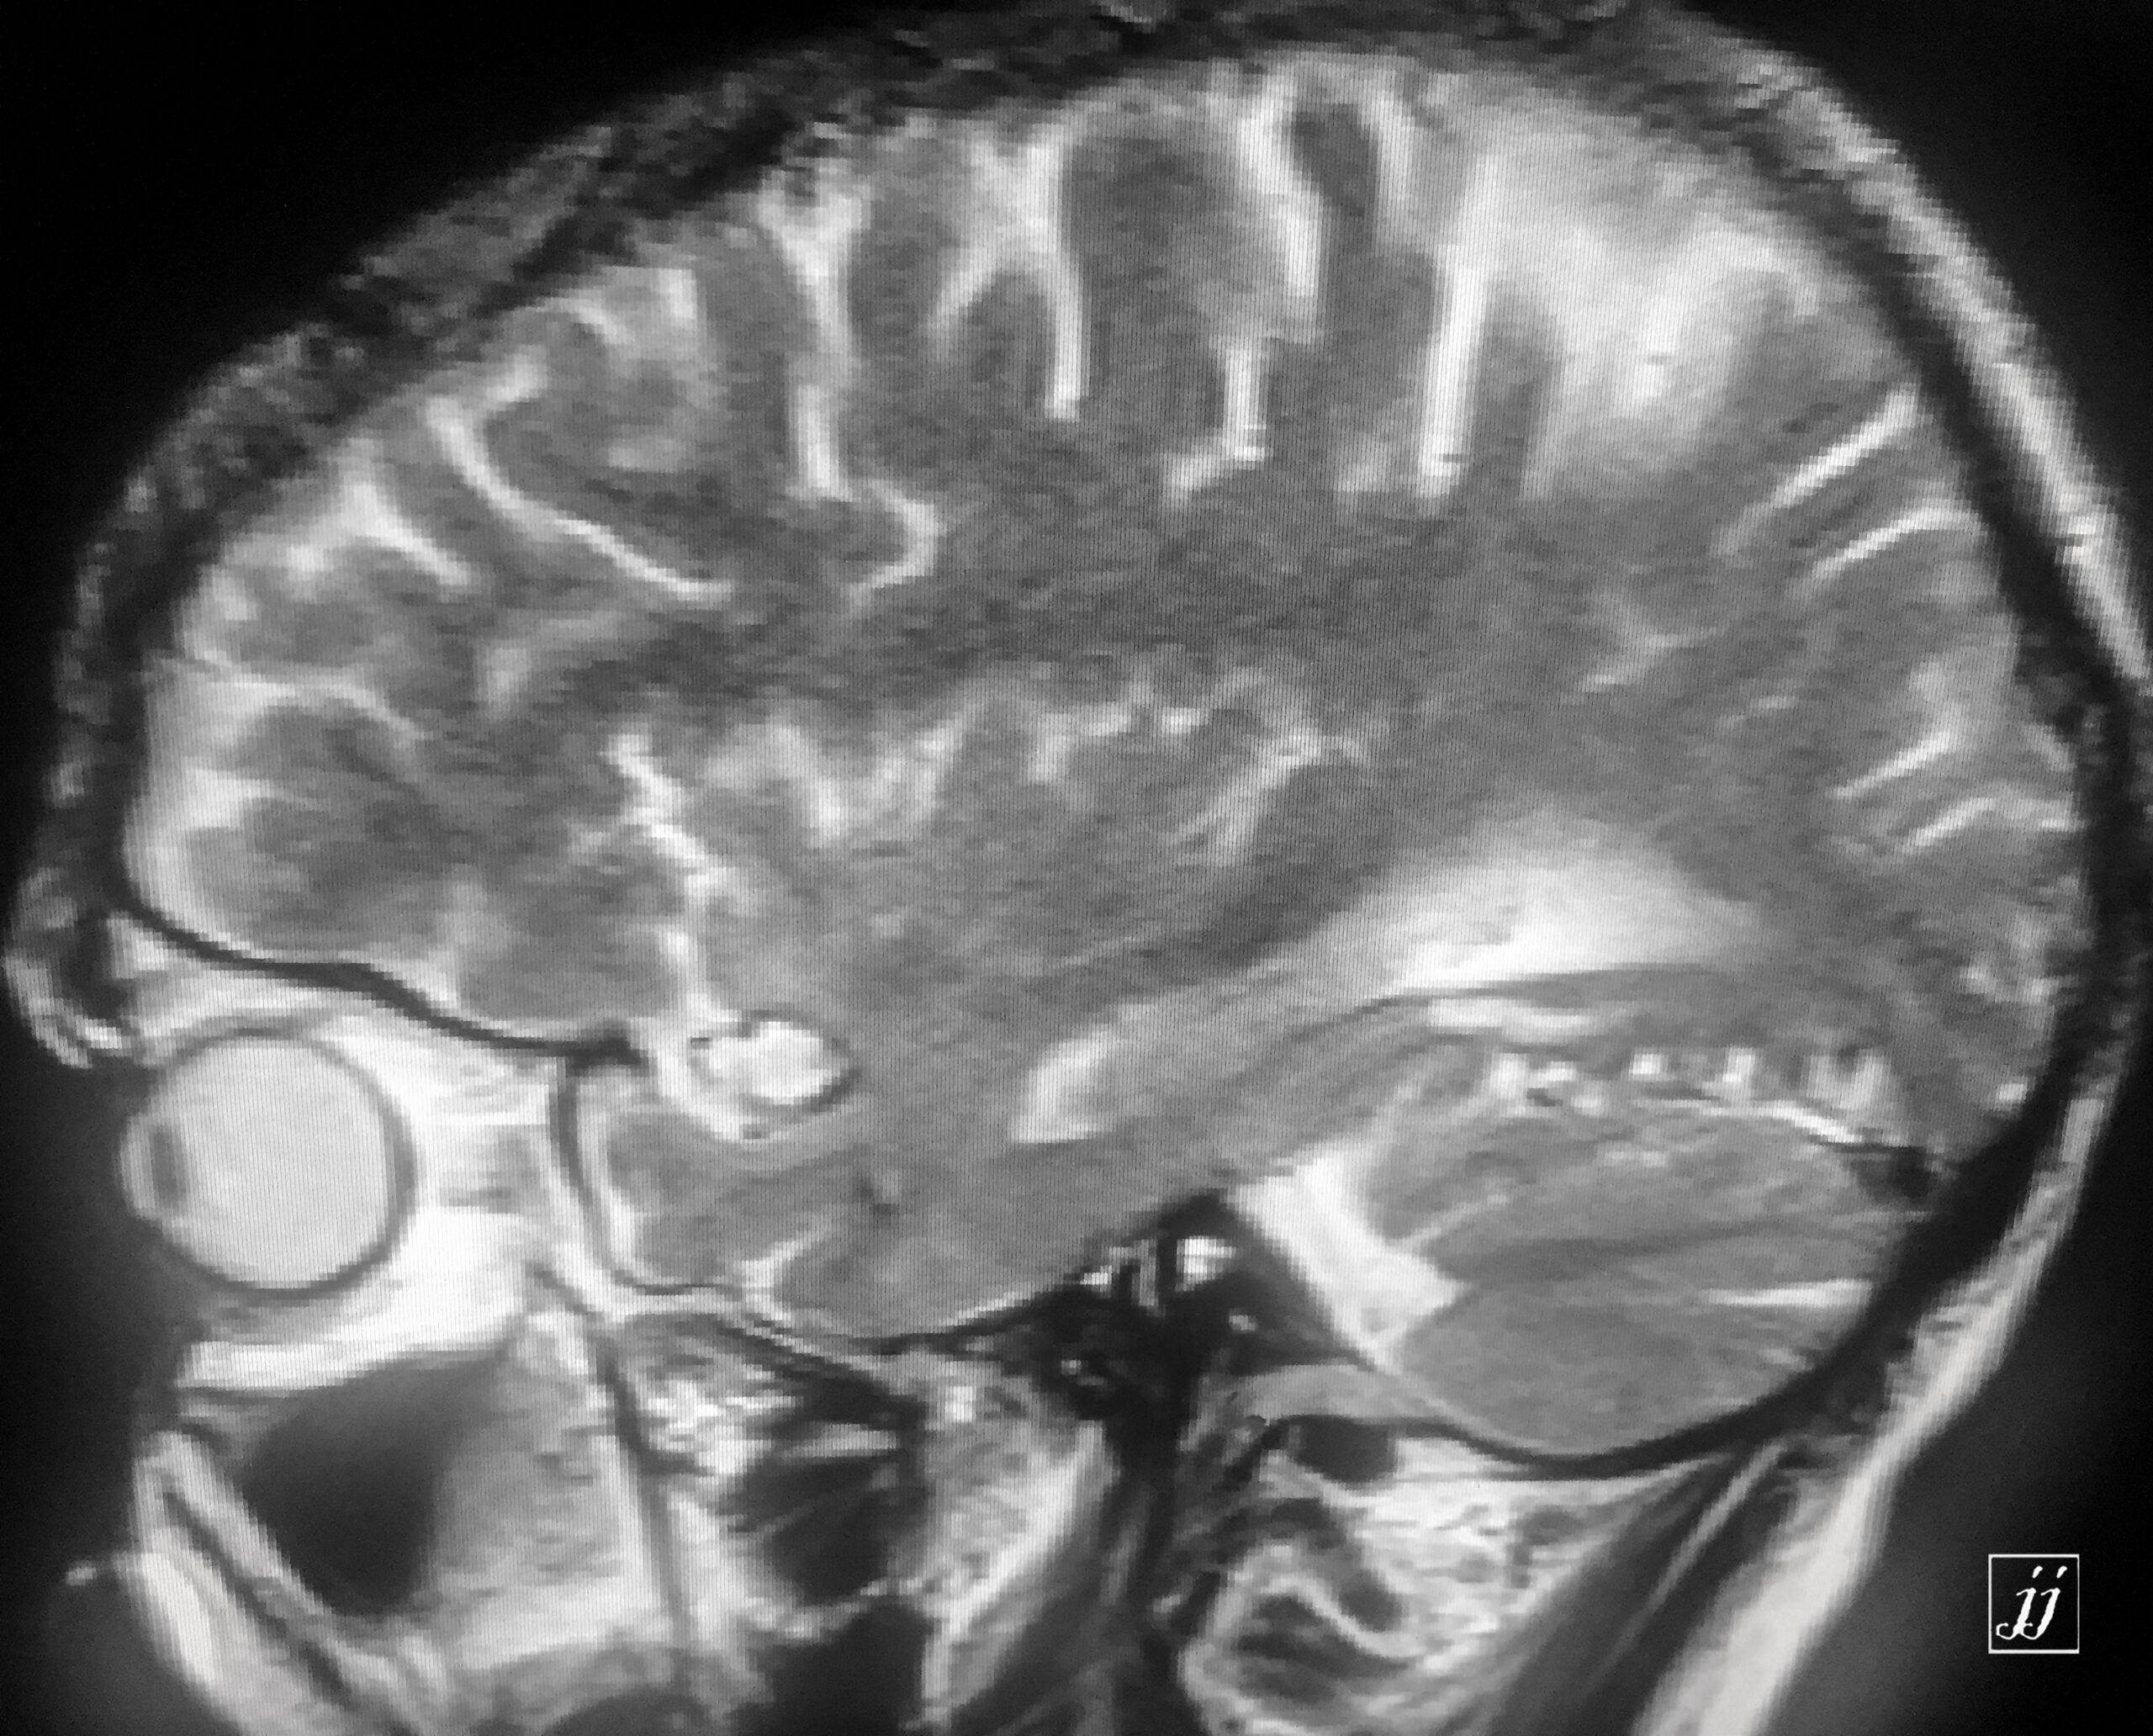

Brain- left mastoid abscess (5)